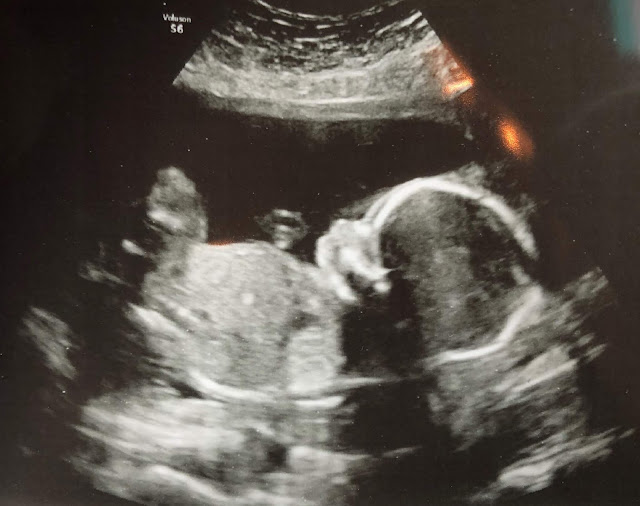

We had my twenty week ultrasound yesterday!

We’re not finding out the gender – we didn’t find out with Henry and Eliza either and we loved the surprise, but I’ve got to say, it’s been more difficult this time around. I sooooo want to know what this baby is, but we’re sticking to our guns and waiting for that delivery room surprise!

Twenty weeks to go!!!